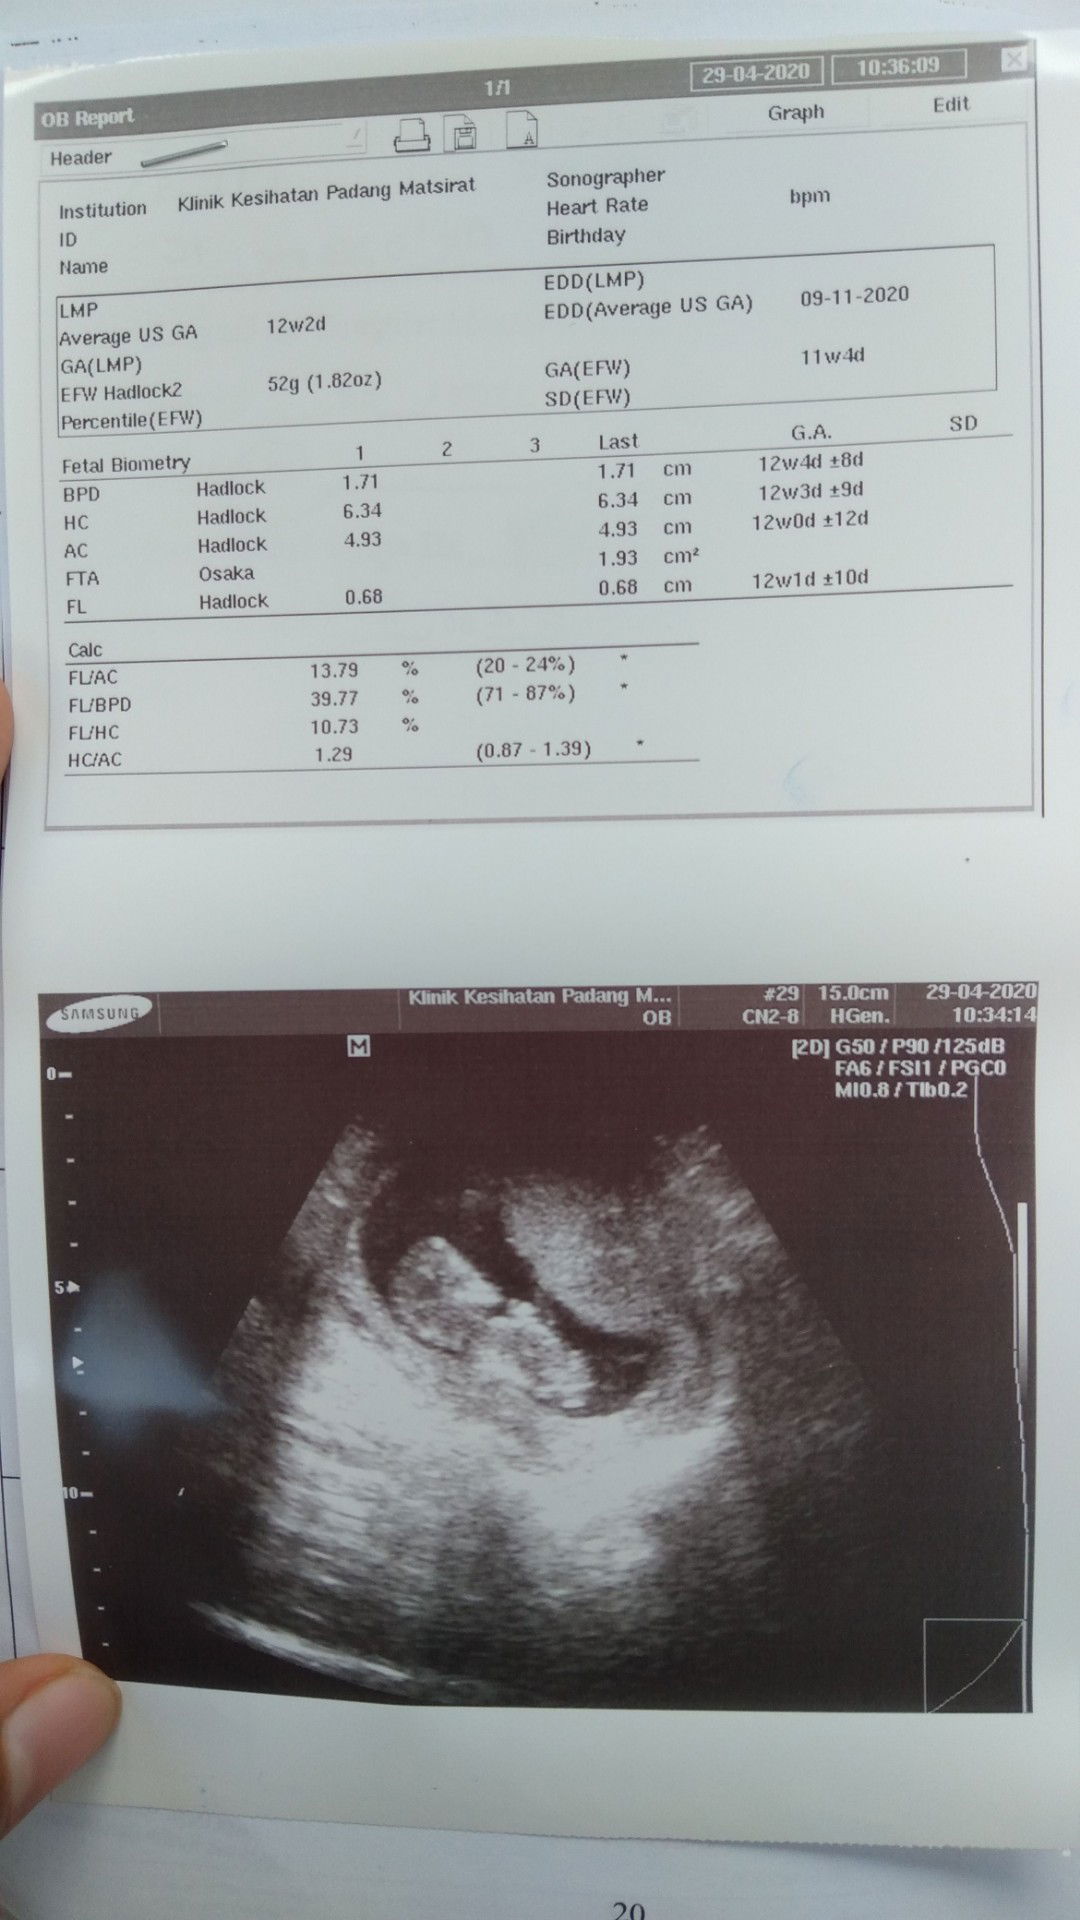

Salam nak tanya. Masa first scan dulu due 23.11.2020. (scan dekat klinik swasta) pastu bila buat buku pink p klinik desa nurse tulis due kat buku pink 19.11.2020. lepastu harini pula kena pergi klinik kesihatan jumpa doktor dan scan. Dan doktor pula bgitau dia dapat due 9.11.2020. pastu lagi 2 minggu doktor suruh pergi scan lagi untuk kepastian due. Ada tak yang pengalaman macamni? Gambar tu gambar scan yang Hari ni.

Masa first scan dapat due 23.11.2020 (scan klinik swasta) masa buat buku pink dekat klinik desa dapat due 19.11.2020. dan harini kena p scan dekat klinik kesihatan jumpa doktor. Dan dapat due 9.11.2020. lepastu doktor cakap due dengan klinik desa jauh beza. Lagi dua minggu kena p scan pulak. Pernah ada pengalaman macam ni tak? Tu gambar yang baru scan harini